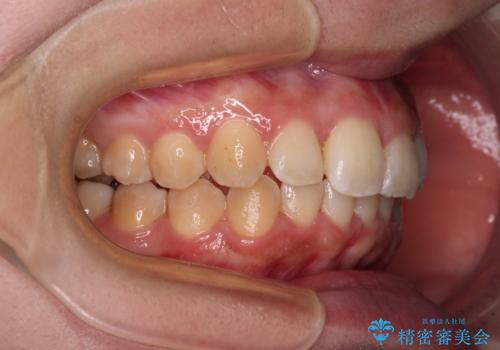

前歯のデコボコをインビザライン矯正で綺麗に改善

- 上下前歯のデコボコを気にして来院された患者様です。

全体的に叢生は軽度であったため、インビザラインにて矯正治療を行うこととしました。

舌の突出癖改善がうまくいかず、途中で舌小帯の切除を行いました。

気になる段差を納得いくまで改善させたため、治療期間は長くなりましたが、綺麗な仕上がりとなりました。